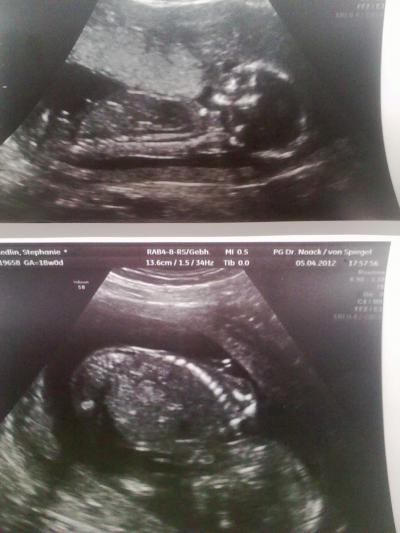

Huhu ihr Lieben, ich hab neue Ultraschallbilder und bin total glücklich

Bild zu Neue Ultraschallbilder :) - Forum für September - Mamis